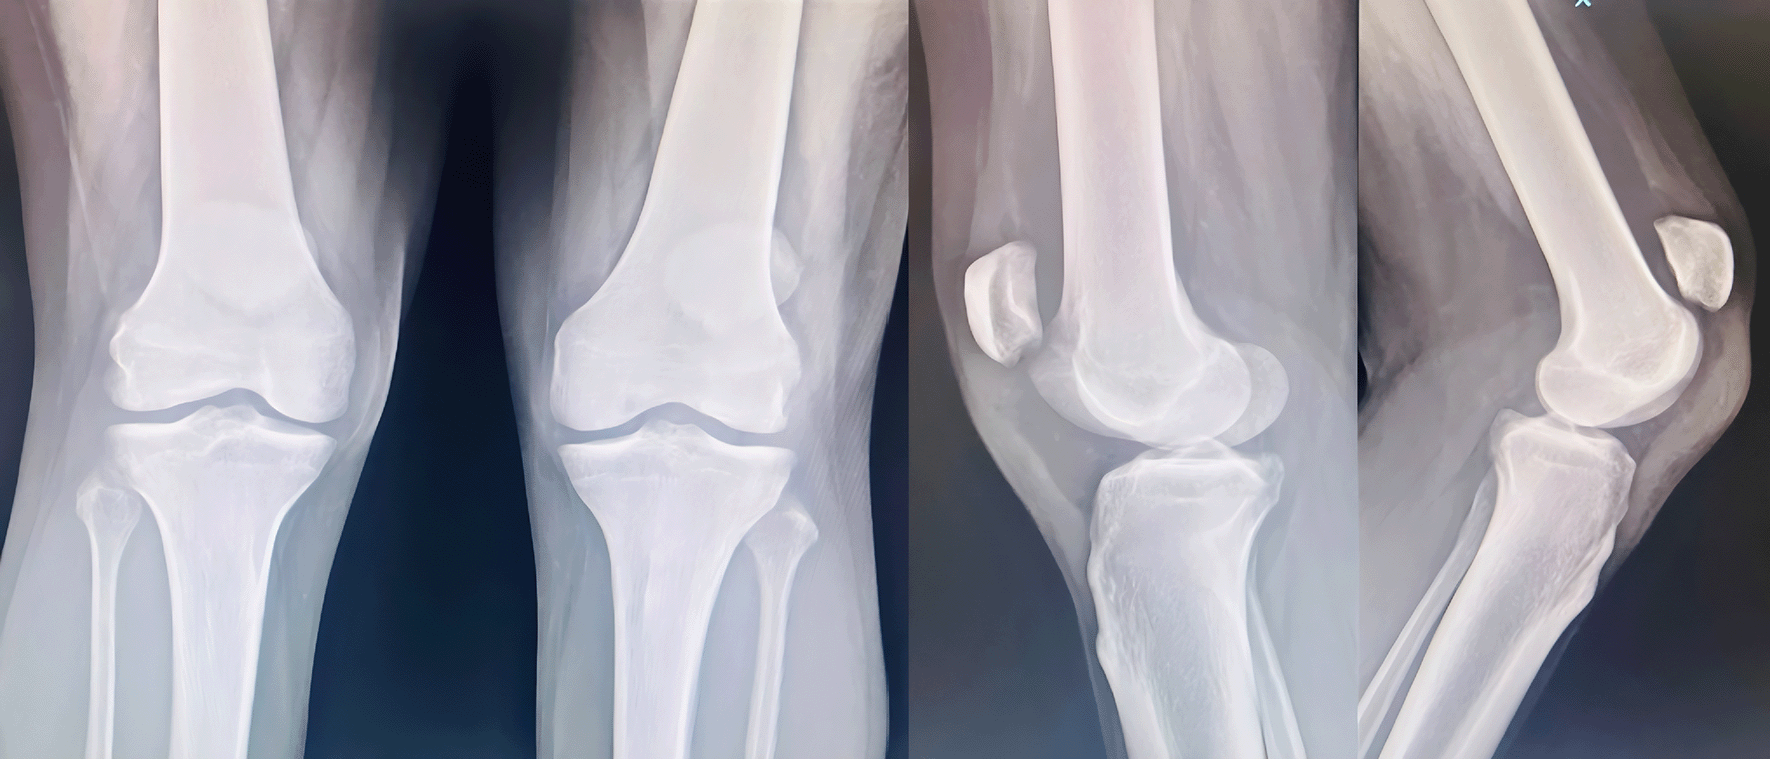

A 44-yr old male with ESRD secondary to immunoglobinA nephropathy with a history of allograft rejection during three weekly hemodialysis sessions for 10 years presented with complaints of right elbow extension weakness following trivial trauma. Physical examination revealed swelling of the right elbow with grade 0 power in the elbow extensor mechanism. Radiographs showed an avulsed triceps tendon (Figure 3).

Figure 3. Anteroposterior and lateral radiographs of Case 2 with avulsed triceps tendon.

He underwent open repair of the triceps tendon with a suture anchor inserted in the olecranon after excision of the devitalized tongue of the tissue (Figure 4). The elbow was immobilized in an above elbow slab at approximately 110° for 6 weeks, after which active mobilization was started. The last follow-up at 7 months revealed grade 5/5 power with full elbow ROM.

Figure 4. Post-operative radiographs after fixation of tensons using suture anchors.